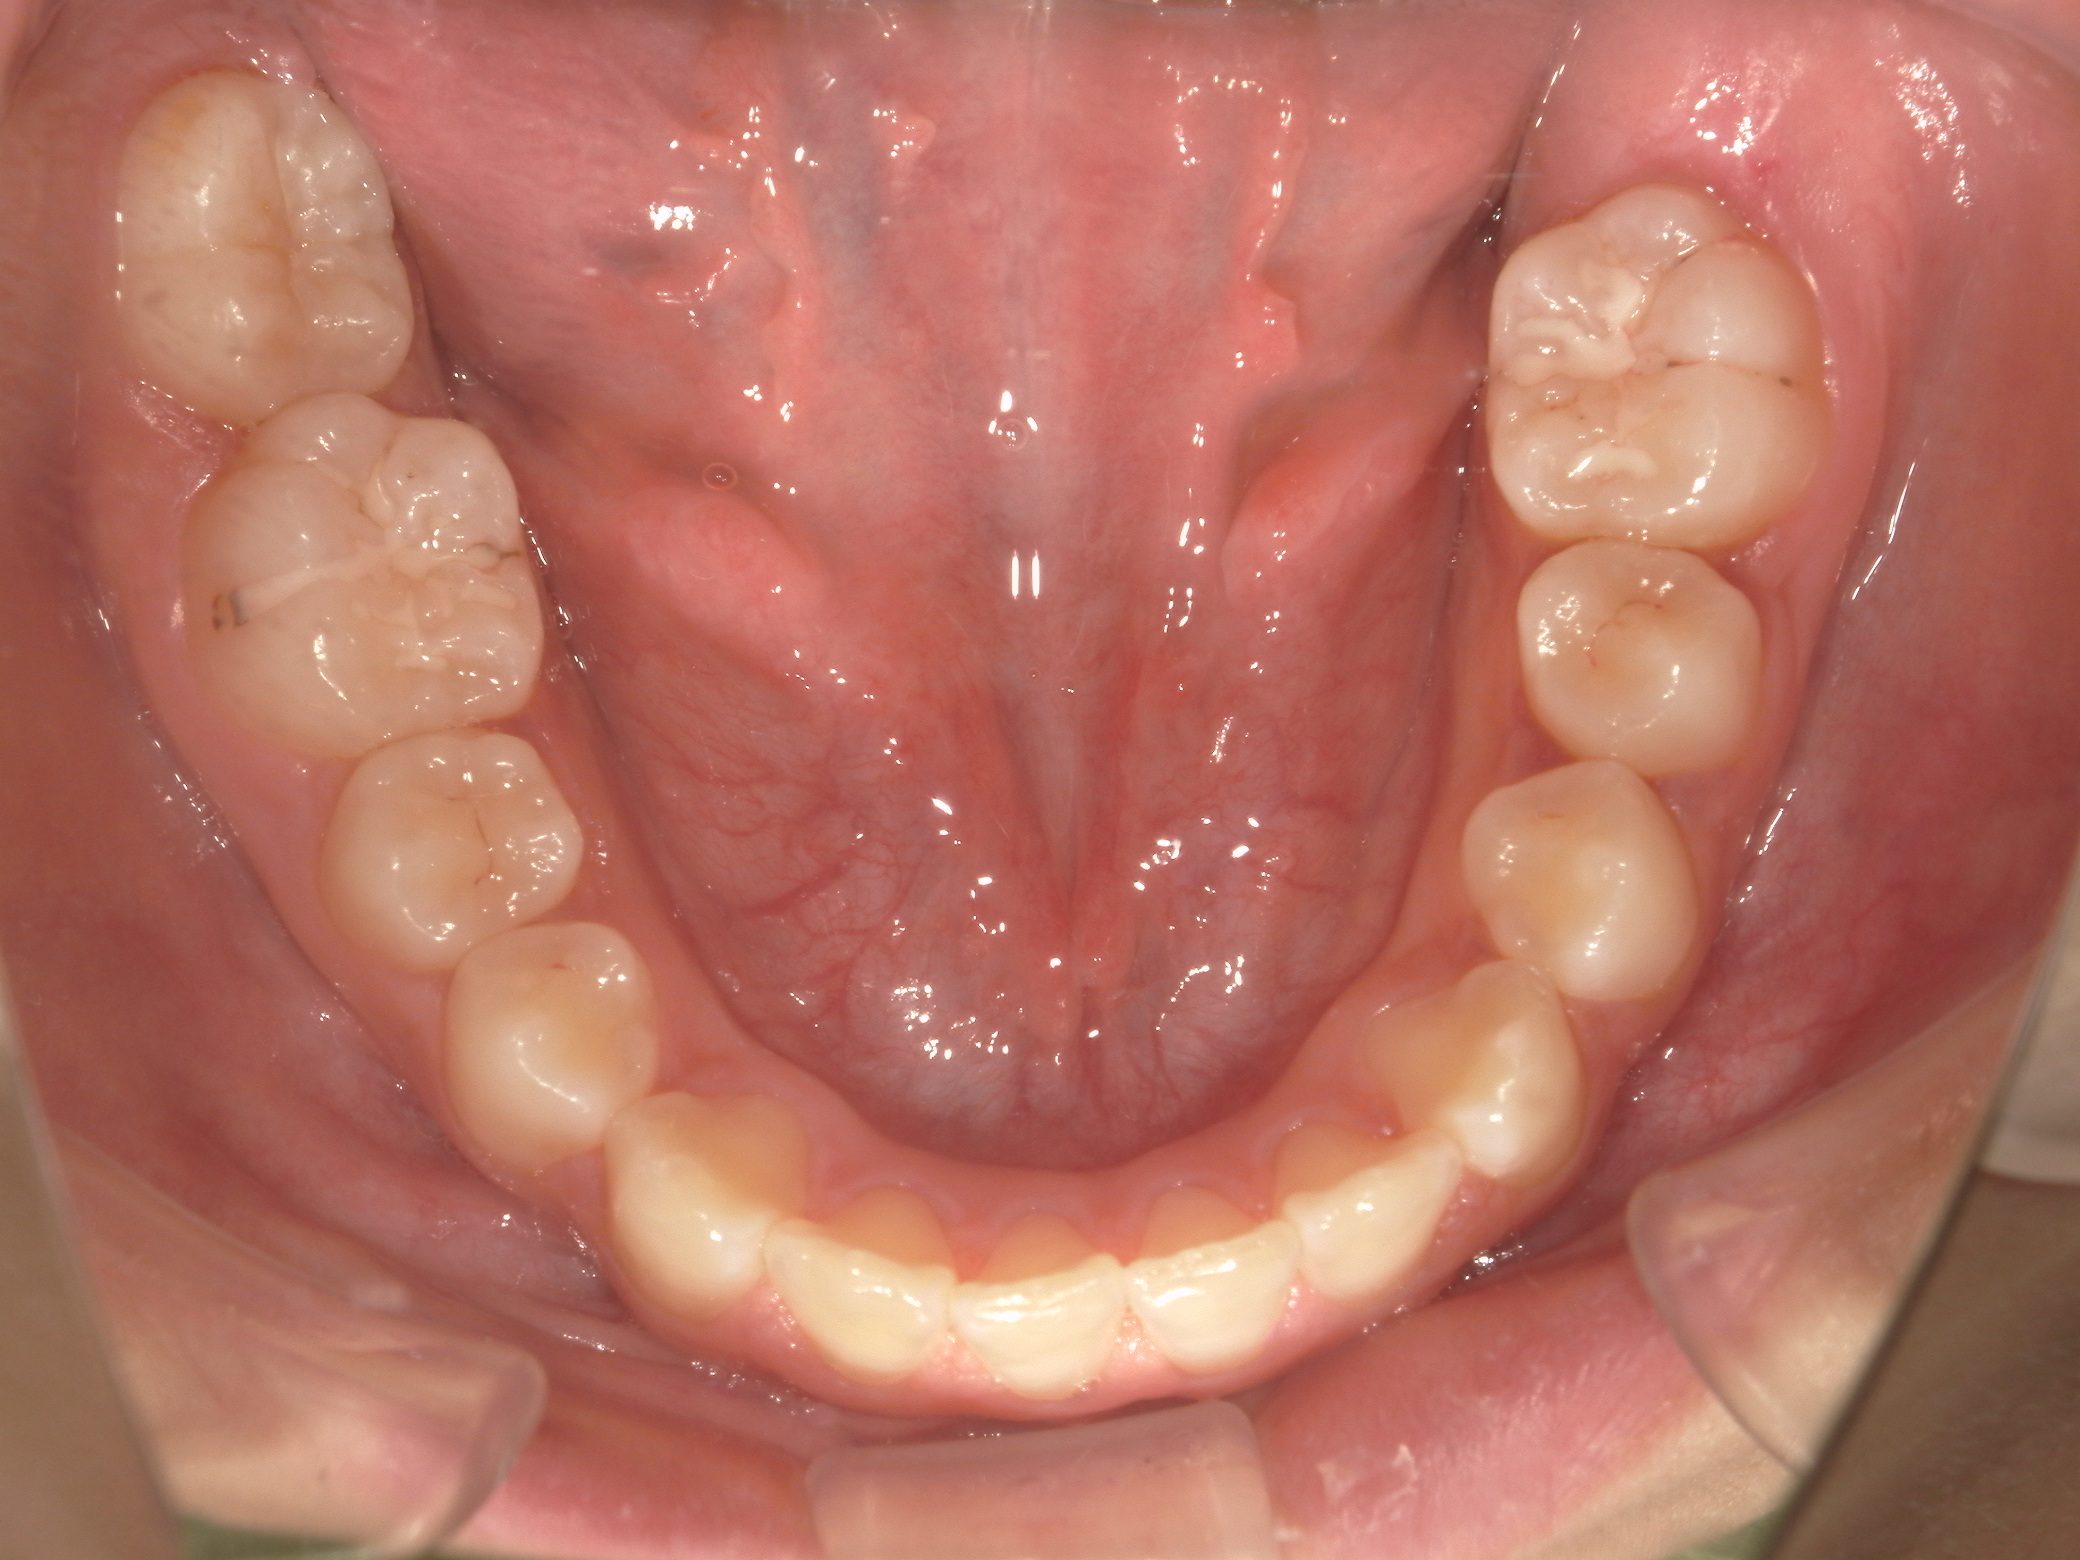

【小学生】 マイオブレース矯正 叢生(でこぼこ)を改善

小学生で開始

マイオブレース

でこぼこ

非抜歯

1期治療のみで改善

Before

After

治療期間

2年

治療開始

8歳

種類

マイオブレース矯正

使用装置

マイオブレース 3Dリンガルアーチ

コメント

非抜歯で 治療期間は2年

治療後4年たっていますが、綺麗な歯並びを維持しています